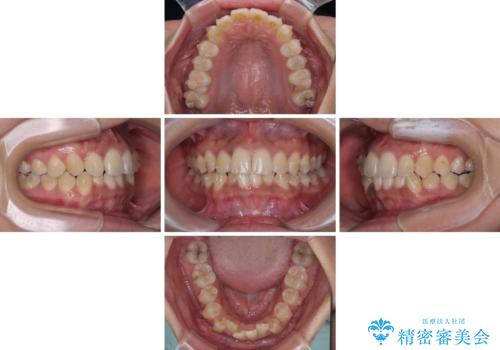

前歯のデコボコと隠れてしまう下顎前歯 インビザラインですっきりと改善

インビザライン発注後に長期滞在先から2年間ほど帰国することができず、インビザラインの有効期限内に終了できるのか不安でしたが、矯正治療開始後は十分な装着時間を達成され、1年未満の期間で無事に終えることができました。